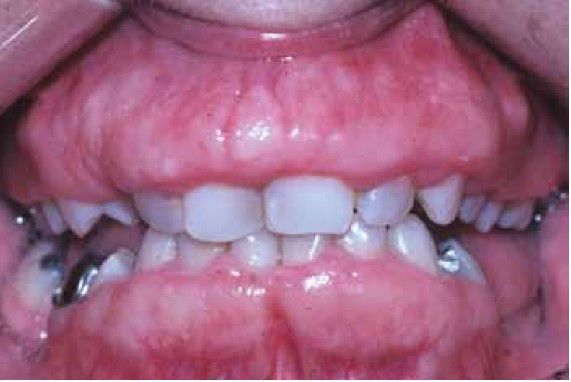

Hereditary Gingival Fibromatosis

Hereditary Gingival Fibromatosis in a 37 year-old white mother. The enlarged gingiva is firm and appears normal in color and texture. The patient underwent two surgical interventions as a teenager with poor long-term results.